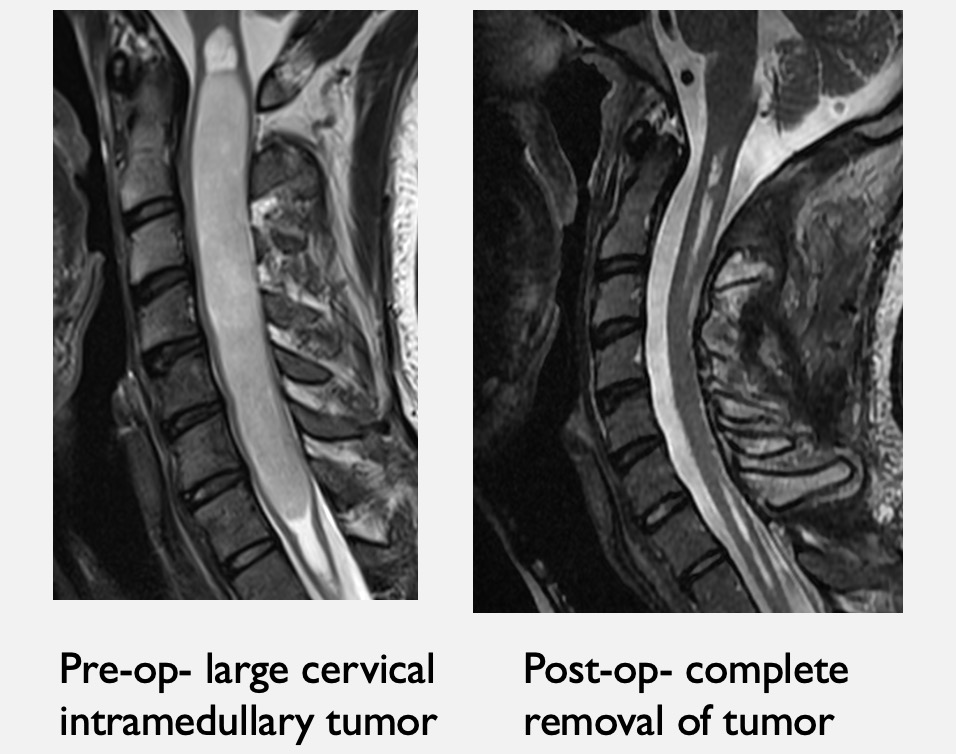

From www.paulcmccormick.com

Dr. McCormick presents at Neuroscience Grand Rounds on Spinal Tumors at Tufts Medical Center Spine Surgeons We use the latest techniques — like gamma knife surgery and microsurgical instruments as thin as a human hair — to address all kinds of neurologic and spinal conditions, from spine surgery to. Neel madan, interventional neuroradiologist, director of radiology residency program, tufts medical center, boston, ma. From alleviating mild neck and back discomfort to performing minimally invasive spinal surgery,. Tufts Medical Center Spine Surgeons.